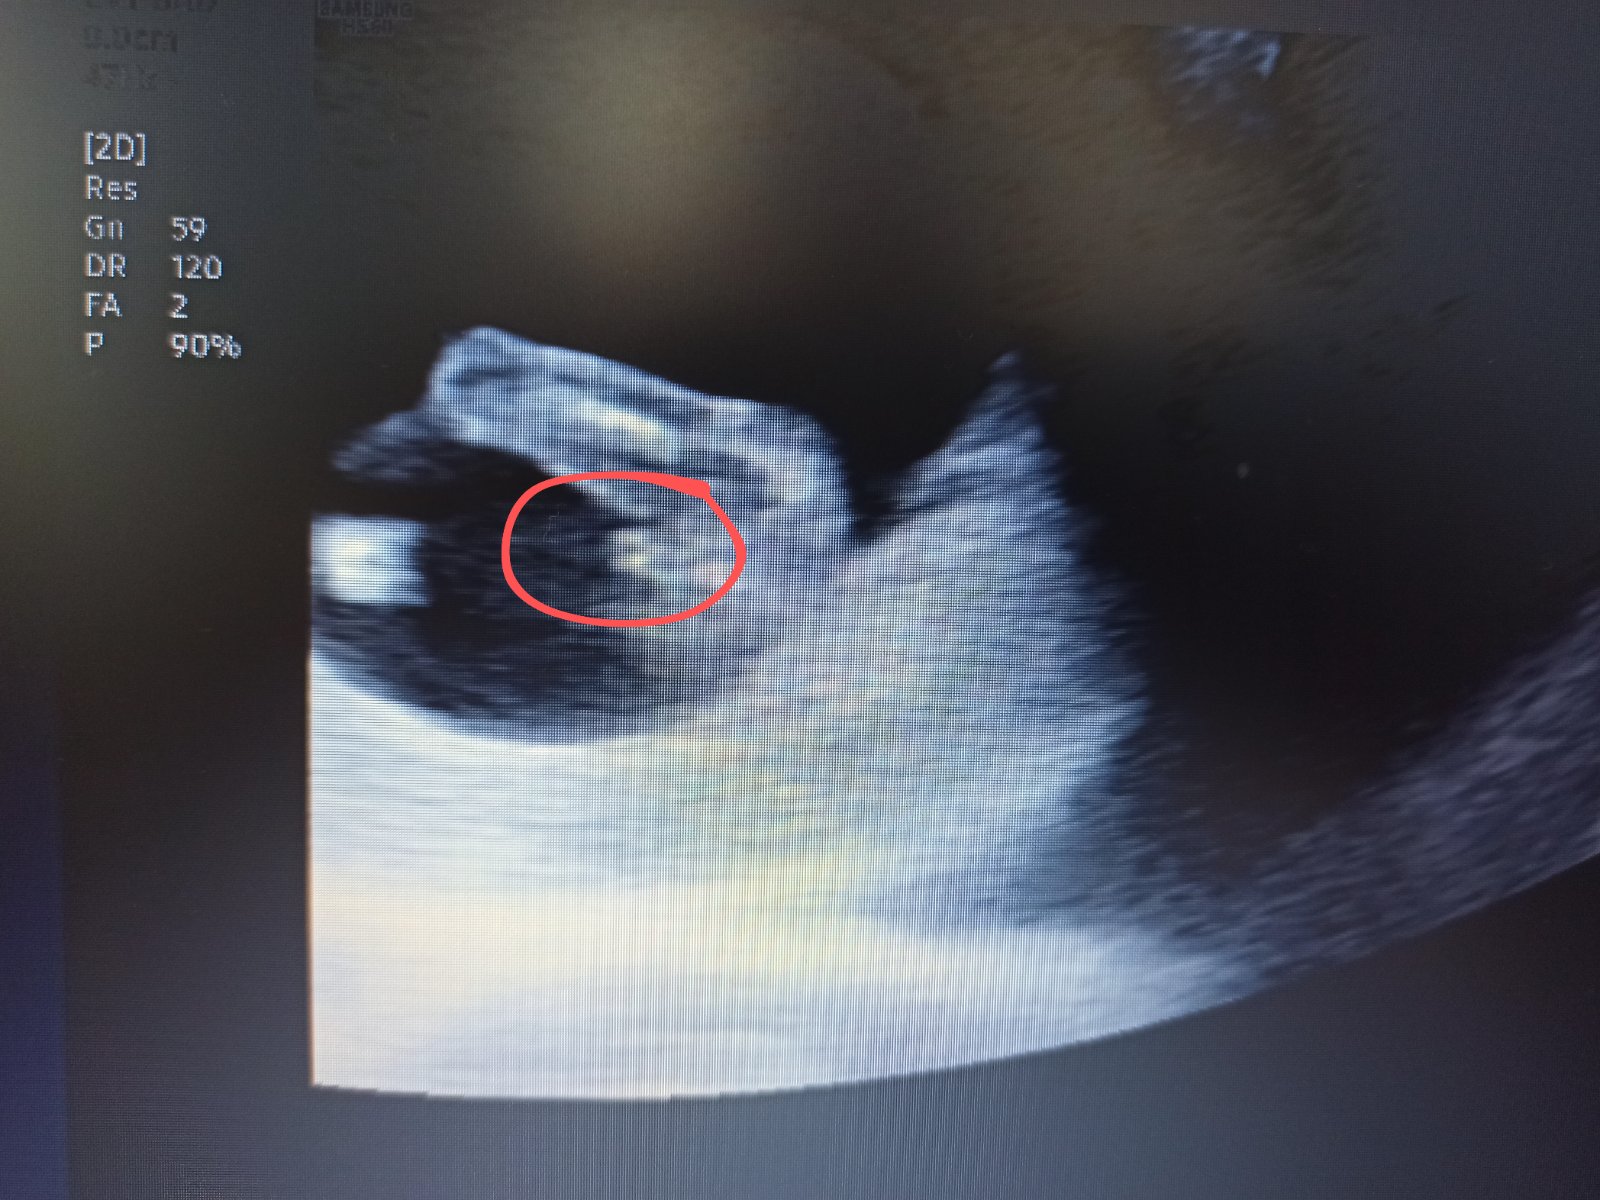

Já podle svého už však nevím, zda se jedná o tento výběžek nebo jestli je to třeba nožička... :D Nemáte někdo zkušenost? 🙂 Určitě nečekám diagnózu, jen by mě zajímala Vaše zkušenost a zda jste na svém ultrazvuku neviděly třeba něco podobného. 🙂

Já bych podle toho svého tipla, ze by to mohla být holčička, ale třeba je to jen mé vymodlené přání. :D

Jsem nedočkavá, až se to u svého doktora dozvím 😍 můj screening pro zajímavost v příloze, máte tip? Za